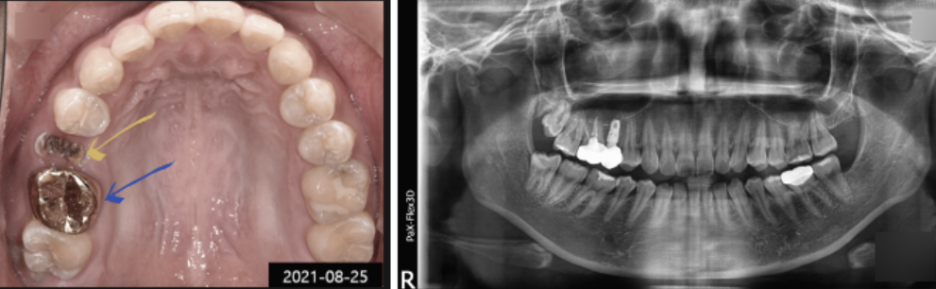

타 병원에서 치료받았던 치아에 문제가 생겨 내원하신 환자분의 사진입니다.

수일 전부터 통증이 심해서 식사도 제대로 못할 정도였는데, 보철물이 떨어져서 급하게 저희 병원을 찾아주셨습니다.

아래 사진에서 노란색 화살표를 보시면, 크라운이 탈락한 내부에 충치가 심한 것을 확인하실 수 있는데요.

내부 충치 때문에 보철물이 탈락한 것으로 보입니다.

제 경우 오래된 보철물을 교체해야 할 때 자연치아를 최대한 살리는 방향으로 진행하고 있지만,

이 환자분의 경우 자연치아를 살리기엔 이미 충치가 많이 진행되어 임플란트 교체가 불가피한 상황이었습니다.

그래서 환자분께 잘 설명해 드리고 남아있는 치아를 발치한 다음 임플란트를 진행하게 되었는데요.

사후관리의 중요성에 대해 환자분께 잘 설명해 드리긴 했지만, 재발방지 및 관리를 위해 SCRP 타입으로 진행하게 되었습니다.

SCRP 타입은 나사구멍을 통해 분리와 장착이 가능해서 사후관리 및 유지 보수에 유용하다는 장점이 있습니다.

그리고 골드 크라운이 씌워져 있던 어금니(파란색 화살표)는 내부 충치치료를 꼼꼼하게 해드린 다음,

주변 치아색과 잘 어울리는 지르코니아 크라운으로 교체해 드렸습니다.